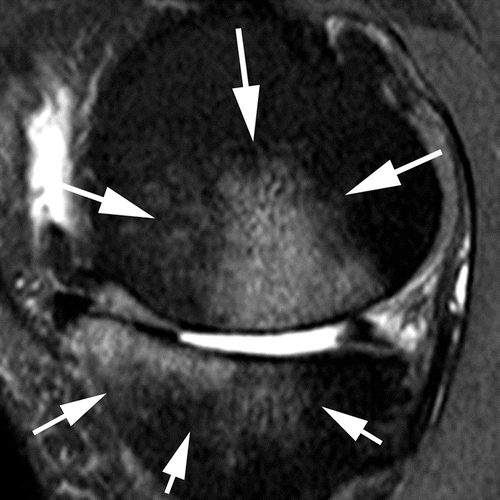

BML assessment according to size

Grade 1

Grade 2

Grade 3